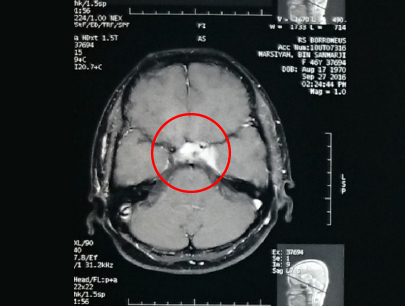

(Perempuan, 14 tahun)

Diagnosis: Malformasi Arteri-Vena Oksipital Kanan

Sebelum Gamma Knife

• Nyeri Kepala

3 bulan Setelah Gamma Knife

• Kebutaan menetap

• Penonjolan mata kiri berkurang

Diameter Nidus: 1.5 cm

Nidus tidak ada